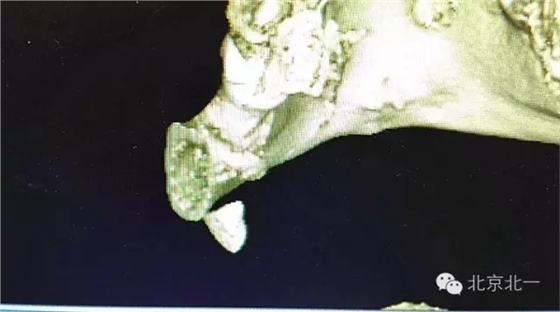

圖三:BCBT重建可見牙根貼在下頜骨下緣舌側(cè)面,接近頜下間隙